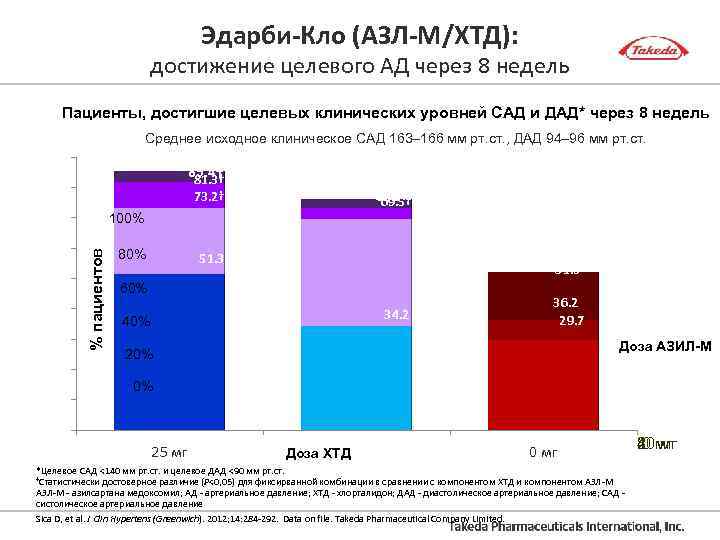

Эдарби-Кло (АЗЛ-М/ХТД): достижение целевого АД через 8 недель Пациенты, достигшие целевых клинических уровней САД и ДАД* через 8 недель Среднее исходное клиническое САД 163– 166 мм рт. ст. , ДАД 94– 96 мм рт. ст. 85. 4† 81. 3† 73. 2† 76. 2† 73. 1† 69. 5† % пациентов 100% 80% 51. 3 51. 9 60% 34. 2 40% 36. 2 29. 7 AZL-M Доза АЗИЛ-М 20% Dose 0% 25 мг CLD Dose 12, 5 мг Доза ХТД 0 мг *Целевое САД <140 мм рт. ст. и целевое ДАД <90 мм рт. ст. †Статистически достоверное различие (P<0, 05) для фиксирванной комбинации в сравнении с компонентом ХТД и компонентом АЗЛ-М - азилсартана медоксомил; АД - артериальное давление; ХТД - хлорталидон; ДАД - диастолическое артериальное давление; САД - систолическое артериальное давление Sica D, et al. J Clin Hypertens (Greenwich). 2012; 14: 284 -292. Data on file. Takeda Pharmaceutical Company Limited. 80 мг 40 мг 20 мг

Эдарби-Кло (АЗЛ-М/ХТД): достижение целевого АД через 8 недель Пациенты, достигшие целевых клинических уровней САД и ДАД* через 8 недель Среднее исходное клиническое САД 163– 166 мм рт. ст. , ДАД 94– 96 мм рт. ст. 85. 4† 81. 3† 73. 2† 76. 2† 73. 1† 69. 5† % пациентов 100% 80% 51. 3 51. 9 60% 34. 2 40% 36. 2 29. 7 AZL-M Доза АЗИЛ-М 20% Dose 0% 25 мг CLD Dose 12, 5 мг Доза ХТД 0 мг *Целевое САД <140 мм рт. ст. и целевое ДАД <90 мм рт. ст. †Статистически достоверное различие (P<0, 05) для фиксирванной комбинации в сравнении с компонентом ХТД и компонентом АЗЛ-М - азилсартана медоксомил; АД - артериальное давление; ХТД - хлорталидон; ДАД - диастолическое артериальное давление; САД - систолическое артериальное давление Sica D, et al. J Clin Hypertens (Greenwich). 2012; 14: 284 -292. Data on file. Takeda Pharmaceutical Company Limited. 80 мг 40 мг 20 мг